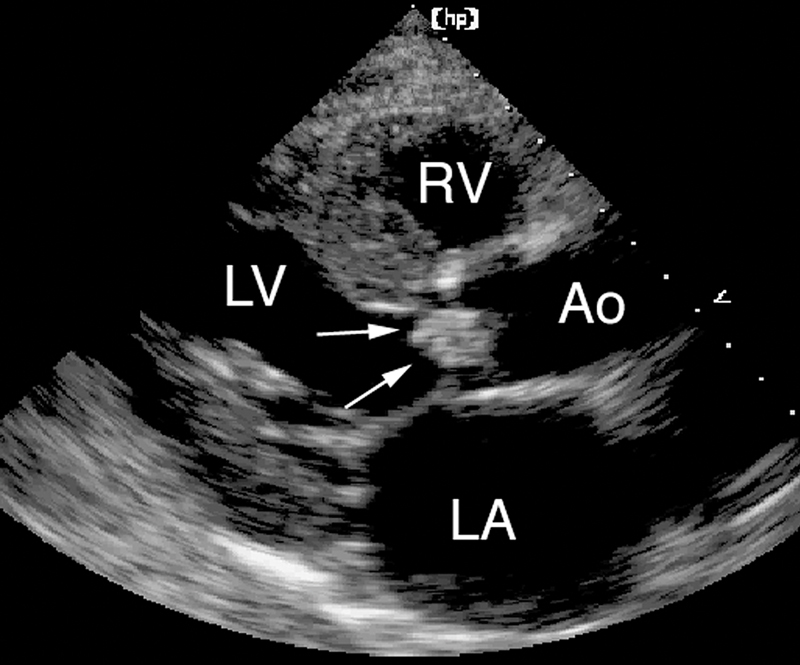

فحوصات تشخيصية لبعض امراض القلب والشرايين التاجية